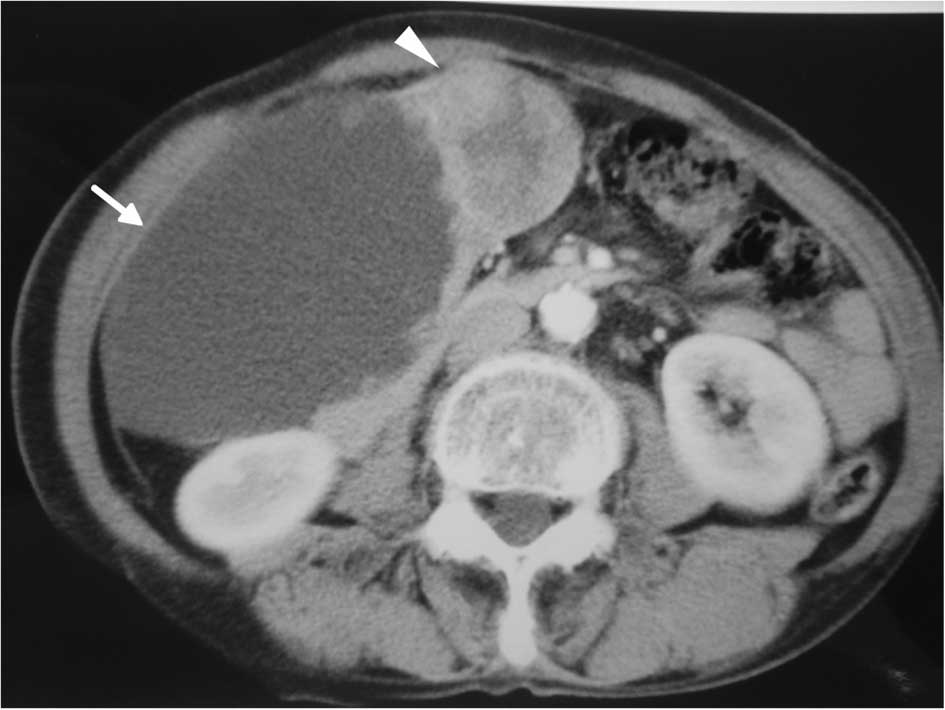

A 79-year-old Japanese female suffering from upper abdominal pain and distention was admitted to our hospital. The patient had previous illness of note nor a family history of disease. A large mass was palpable in the right upper quadrant of the abdomen. The patient’s lactate dehydrogenase was elevated to 413 IU/l (normal range <230), and two serum tumor markers, carcinoembryonic antigen (CEA) and carbohydrate antigen 19-9 (CA19-9), were both elevated at 3.4 ng/ml (normal range <2.5) and 1465.3 U/ml (normal range <37), respectively. Abdominal radiography showed an oval radio-opaque shape of 15 cm in diameter in the right upper abdomen (Fig. 1). Ultrasonography (Fig. 2) and computed tomography (CT) (Fig. 3) revealed the tumor to be a monolocular cyst with an irregular wall thickness of 15 cm in diameter concomitant with a solid mass of 8 cm in diameter around the gallbladder bed, suspected to be a tumor originating from the gallbladder. Endoscopic examinations of the alimentary tract showed no abnormalities. During celiotomy, the tumor with a large pale gray cystic component was identified at the fundus of the gallbladder. The tumor fibrously adhered to the liver, duodenum, and greater omentum, but it appeared to have only partially infiltrated into the transverse colon. A number of small nodules suspected to be tumor dissemination were scattered on the peritoneum. Gallbladder cancer with peritoneal dissemination was diagnosed. Although curative resection for the tumor was impossible, a simple cholecystectomy was performed that included the tumor without systematic lymphadenectomy, and a partial resection of the transverse colon was added due to its tight adhesion by the tumor cyst.

Figure 3

Enhanced computed tomography showed a large cystic tumor (arrow) with a solid component (arrow head).